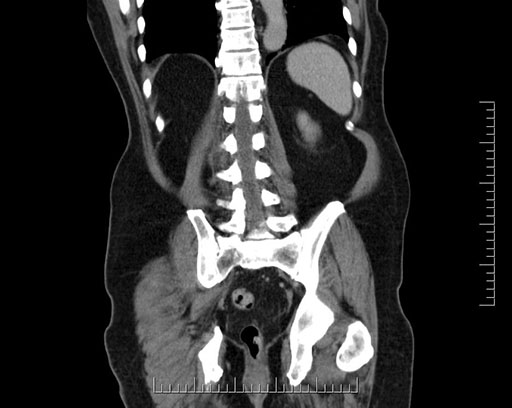

Coronal - stented